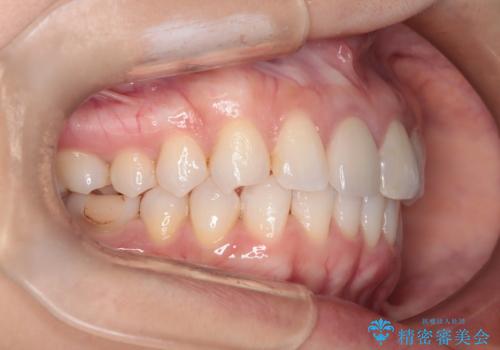

- 前歯のガタつき、変色を主訴に来院された患者様です。術前診査のCT撮影にて、変色した前歯の根の先に病巣があることが判明しました。そこで、マウスピースによる矯正治療と、前歯の根管治療、かぶせ物のやり直し治療を並行して行いました。